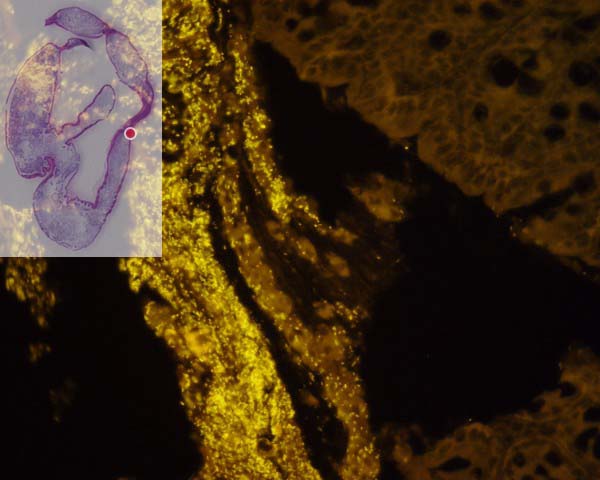

Räumliche Organisation der mukosalen Flora einer gesunden Wildtypmaus in verschiedenen Abschnitten eines Dickdarms

Auf der linken Seite sehen Sie die Ansicht des Schnittes des gesamten Dickdarms einer gesunden 26 Wochen alten Maus. Durch einen Klick auf ein Segment innerhalb des Bildes  wie z.B. Coecum, Appendix, proximales Colon, mittleres Colon, distales Colon, Rectum und der Rückwand gelangen Sie dann zu einer

Reihe von FISH-Bildern, die kontinuierlich entlang der Darmwand aufgenommen sind. Mit der Vor- und Rückwärts-Taste wandern sie schrittweise entlang des Darms.  Der rote Punkt auf dem Übersichtsbild markiert die jeweilige Position des mikroskopischen Feldes.  Die Farben sind real mit einer Nikon Digital Kamera aufgenommen. Bacteroides ist Orange (Cy3), Eubacterium rectale leuchtet rot (Cy5), alle anderen Bakterien haben eine grüne Fluoreszenz. DAPI (blaue Fluoreszenz) färbt die Nukleinsäuren. Wahlweise sind alle drei Bakteriengruppen simultan aufgenommen. Zur besseren Übersicht präsentieren einige Felder ausschließlich Cy3 (Bacteroides) oder Dapi (Nukleinsäuren) Fluoreszenz.